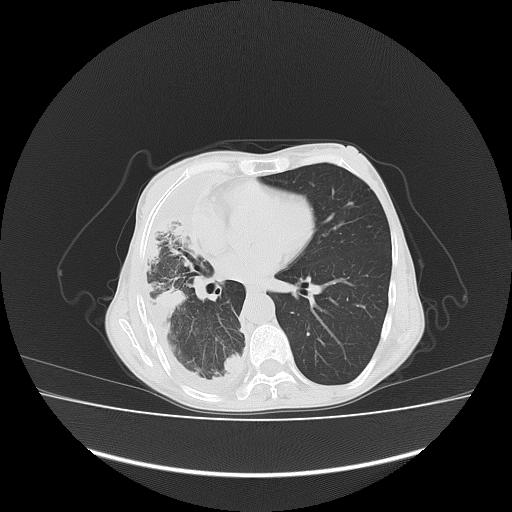

标题: CT16930:女 59 胸痛6个月 胸水脱落细胞学见瘤细胞 [打印本页]

可见多发肺内病灶,且胸膜病灶较多有圆球状而非丘状,多考虑胸膜转移瘤伴胸腔积液,右侧胸廓缩小固定,且部分病灶呈丘状,尚不除外恶性胸膜间皮瘤伴肺内转移

右侧胸膜增厚,局部呈结节状增厚,右侧胸腔少量积液。双肺未见确切肿块影。纵隔未见淋巴结肿大。气管、支气管通畅。考虑右侧胸膜间皮瘤(恶性?)可能性大。不除外癌性胸膜炎。

恶性胸膜间皮瘤伴肺内转移可能性大;或胸膜、肺内均为转移瘤,左肺下叶亦见多发小结节影。

右侧胸廓塌陷,右侧胸膜广泛增厚并见多发胸膜结节,右侧少量胸腔积液并包裹。

右侧广泛胸膜增厚,局部呈结节状增厚,右侧胸腔少量积液。双肺未见确切肿块影。纵隔未见淋巴结肿大。气管、支气管通畅。考虑右侧胸膜间皮瘤(恶性?)可能性大。支持!

右侧胸膜转移瘤,原发灶可能就在在右肺,另外建议检查右侧乳腺.

右胸腔结节均考虑来自胸膜(部分来源于叶裂),考虑胸膜间皮瘤或转移瘤.